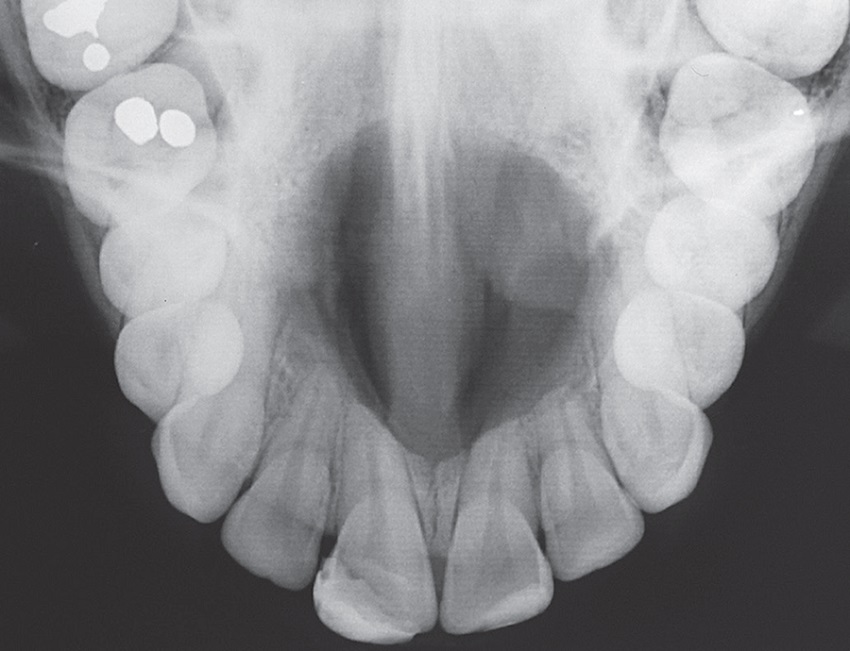

A 25-year-old male patient attended the Stomatology Clinic of the Department of Dentistry of the PUC Minas complaining of a painful swelling in the central region of the hard palate, with three weeks of evolution time. The patient did not present noteworthy systemic alterations. The extraoral examination showed no alterations. In the intraoral examination, we observed the presence of a nodule in the central region of the hard palate, with a soft texture, covered by preserved mucosa and normal coloring (Figure 10). The maxillary occlusal radiograph showed a unilocular radiolucent well-defined lesion, in the anterior region of the maxilla, measuring about 3 cm (Figure 11). Tests of pulp vitality of the teeth close to the lesion were performed to rule out the possibility of inflammatory lesions of endodontic origin. The results were positive, and the diagnostic hypothesis was nasopalatine duct cyst. Under local anesthesia, aspiration of the lesion fluid (positive for translucent fluid) and excisional biopsy were performed, following a surgical protocol similar to the previously reported case (Figures 12 and 13). The material was sent for anatomopathological examination (Figure 14). The histological sections, stained with HE, showed cystic cavity covered by non-keratinized stratified squamous epithelia and fibrous connective tissue capsule with neurovascular bundles, confirming the diagnosis of NPDC.